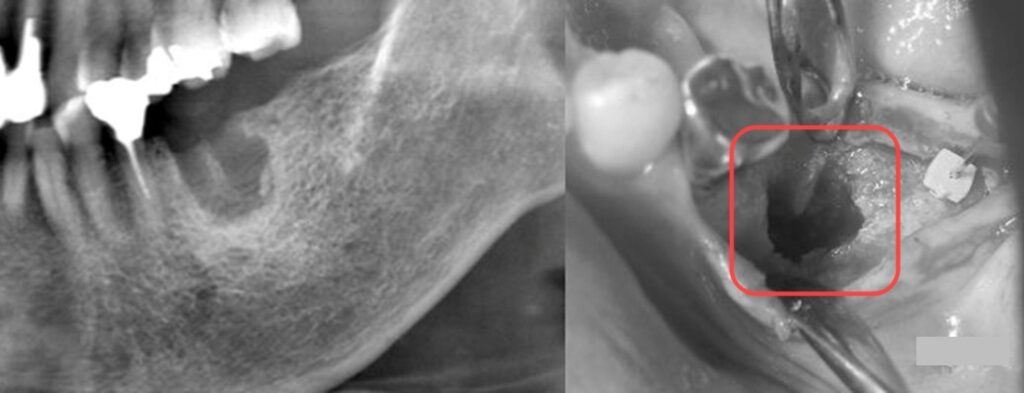

左下の6番(第一大臼歯)を抜歯して3ヶ月が経過した状態です。

抜歯した跡が大きくえぐれたままでインプラントの土台となる骨がありません。

そこでGBR(骨誘導再生法)による欠損部分の再生が必要になります。